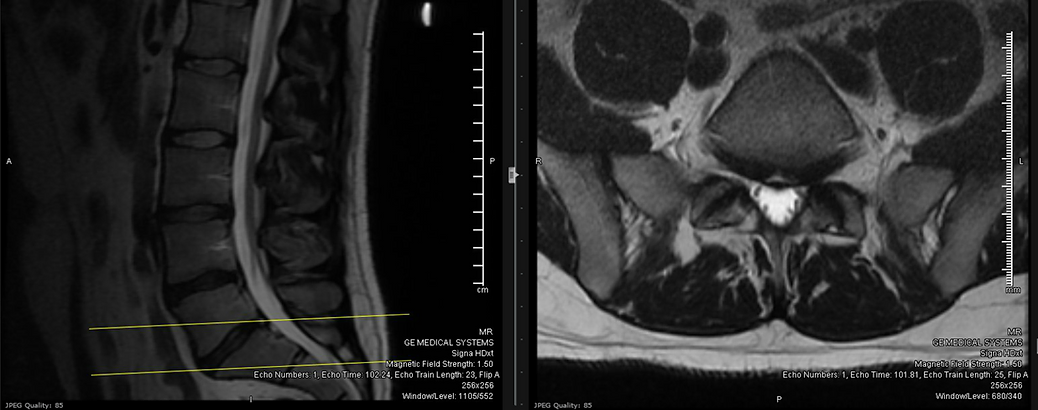

- Obtain a new MRI of the lumbar spine